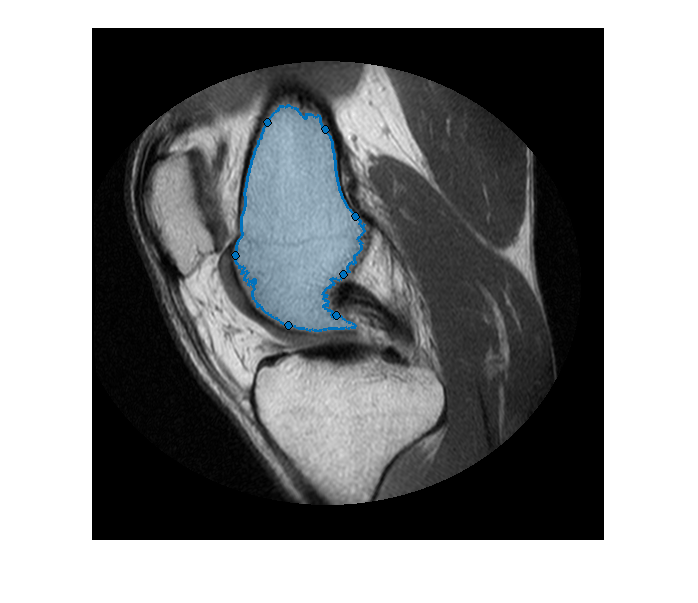

Получите координаты контуров двух сегментированных областей.

blocations = bwboundaries(boneMask,'noholes');

Преобразуйте местоположения, возвращенные bwboundaries к x, y порядок.

pos = blocations{1};

pos = fliplr(pos);

Создайте ROI от руки в сегментированной маске.

hf = drawfreehand('Position', pos);